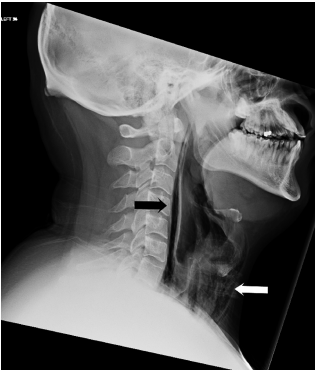

电脑断层扫描发现,该名病患吞下的喷嚏压力,导致喉咙受伤。